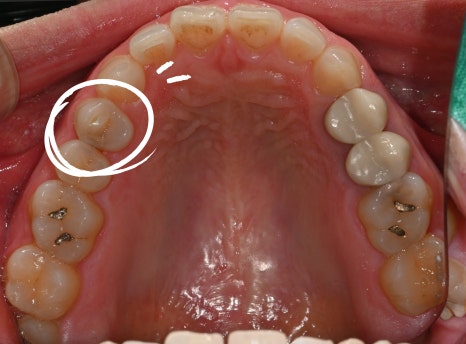

환자분 처음 내원당시

어금니가 꺠지면서 씹을 때 찌릿하고 쑤시는 느낌이 나요

치과에서 찍은 사진과 엑스레이를 확인해보니,

깨진 틈으로 세균이 들어가

신경이 이미 많이 손상된 상태였습니다.